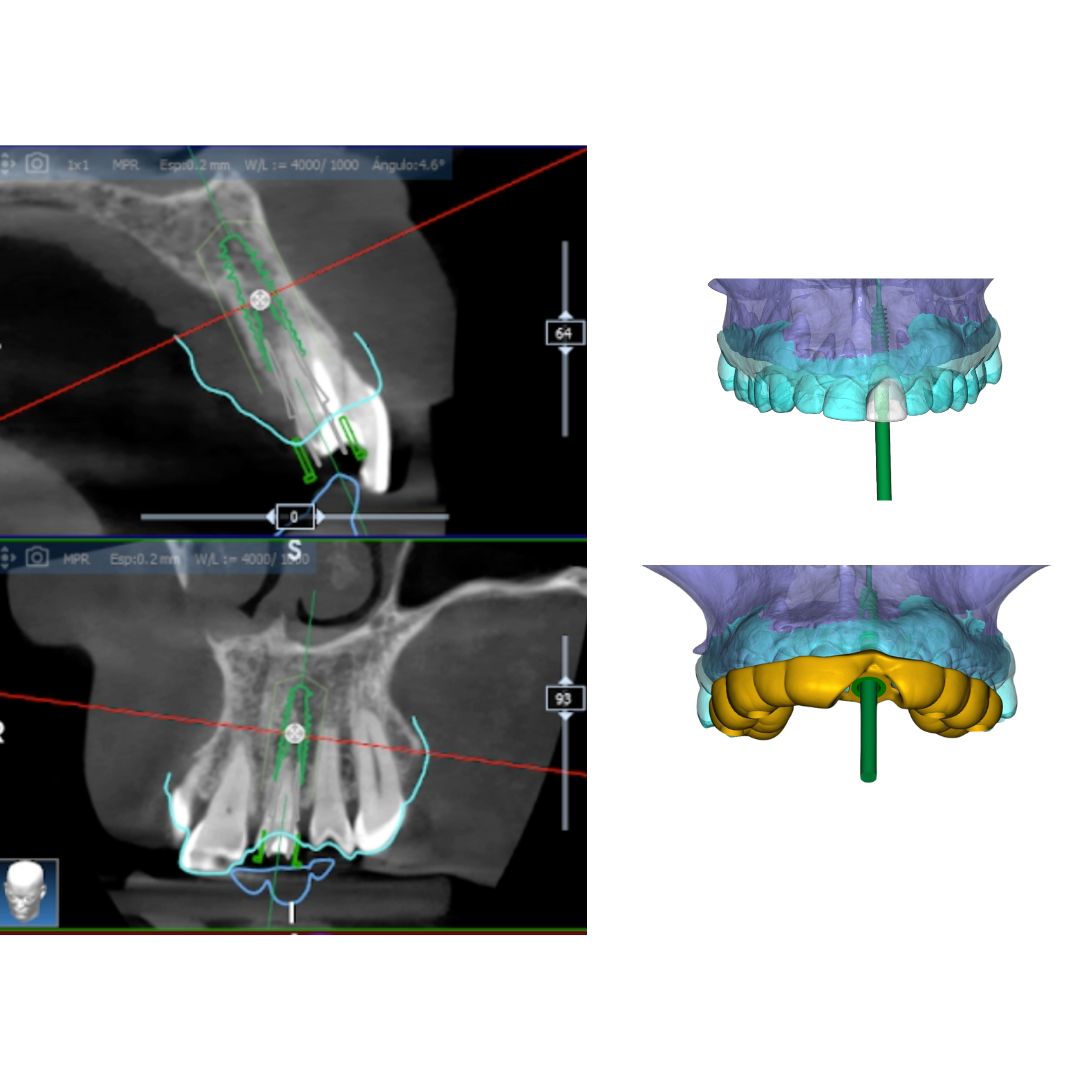

We place implants using guided surgery

This digital planning reduces error margins and enables minimally invasive surgery without extensive incisions. This translates to shorter intervention times, faster recovery, and a more comfortable experience for the patient.

Unlike conventional surgery, guided surgery optimises precision and reduces risks, allowing us to place implants with maximum safety and efficiency. With this technology, we achieve predictable and aesthetic results, ensuring functionality and well-being from day one.